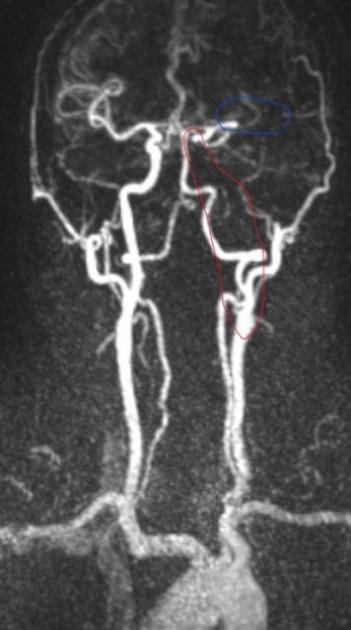

手术过程中,侯建康主治医师发现了王先生血管堵塞的前因后果:左侧颈动脉形成了动脉夹层,夹层进一步诱发血栓形成;而形成的血栓被血流冲刷脱落,进一步堵塞了远端的大脑中动脉。在施洪超主任医师指导下,侯建康主治医师使用抽吸导管将脱落到大脑中动脉的血栓抽吸了出来,随后在动脉夹层的部位植入了一枚支架以重建管腔(见图2)。

图2